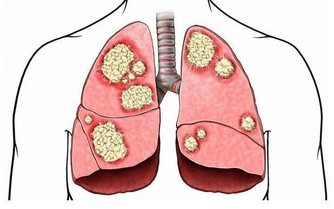

腎臟是人體器官中很重要的一個排毒器官,它一旦出現問題,體內的連環效應就會凸顯,身體就會出現各種各樣的疾病。

據調查統計,目前全球大約有1/10的人慢性腎臟疾病。根據我國最新的流行病學調查結果顯示,在普通人群中慢性腎病的患病率約為12.6%,也就是說,十個人中至少有一人患有慢性腎病。

腎功能隨著年齡增大會逐漸衰退,但是生活中有些不良的生活習慣或行為,也是腎功能受損的重要因素。

這是因為感冒時亂吃抗生素就會讓腎臟受損,可是如果拖著不去治療,看似不太嚴重的感冒、咽喉炎都會引發腎臟疾病。除了常見的呼吸道感染外,其他肺炎、肝炎等感染性疾病也會引發不同類型的腎病。